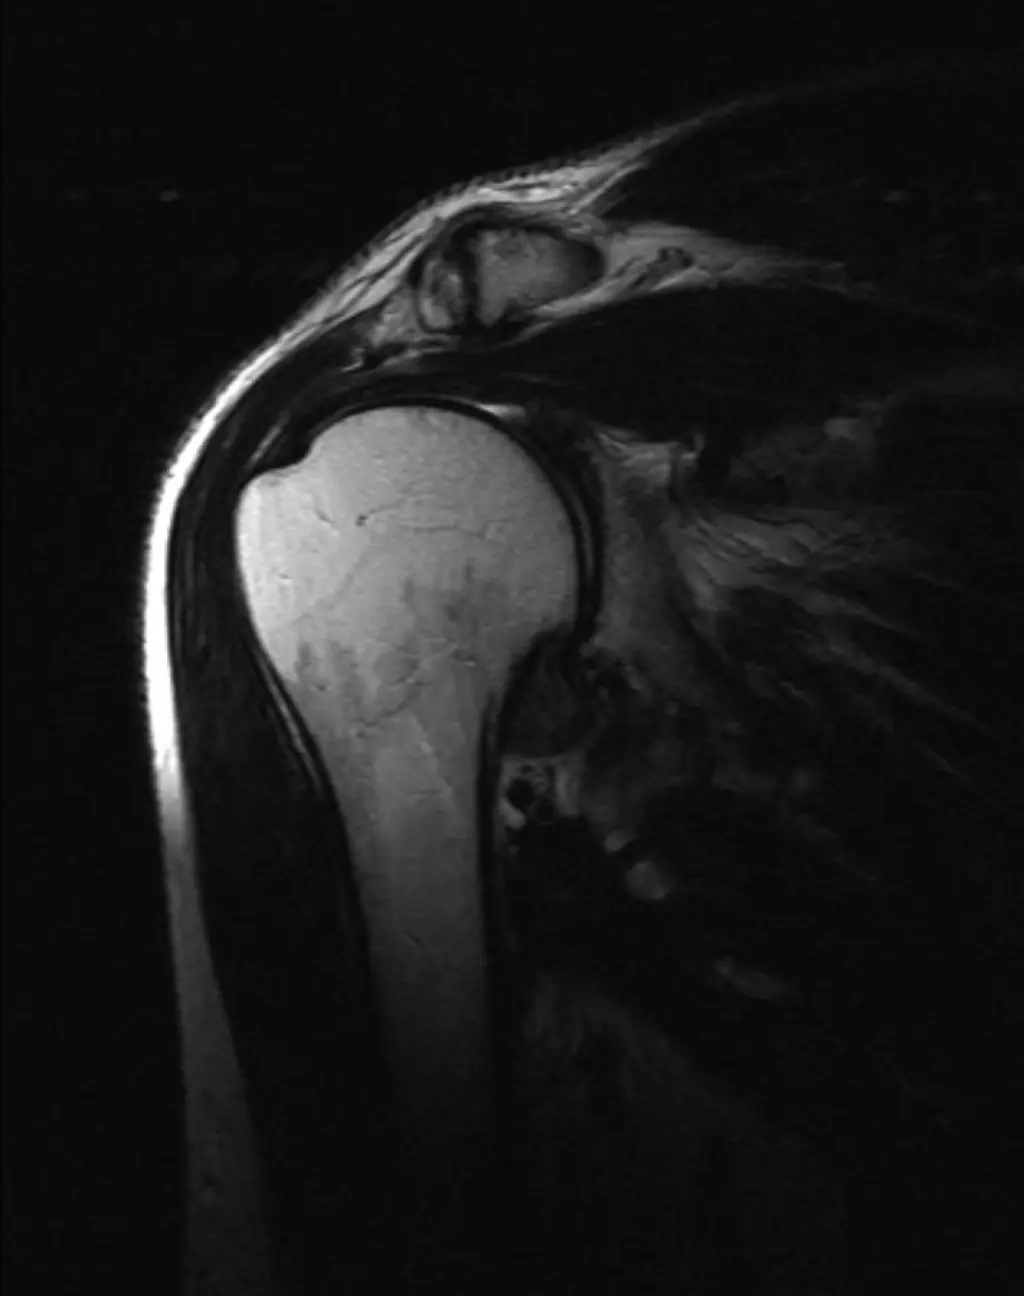

Визуализация костей плечевого сустава, суставной губы, удерживающих сухожилий и связок, регионарных мышц, околосуставных сумок, ключично-акромиального сочленения.

Показания:

— Боли, ограничение подвижности

— Дегенеративные и воспалительные изменения суставов (артрозы, артриты)

— Травматические повреждения элементов сустава

— Повреждения связок, сухожилий